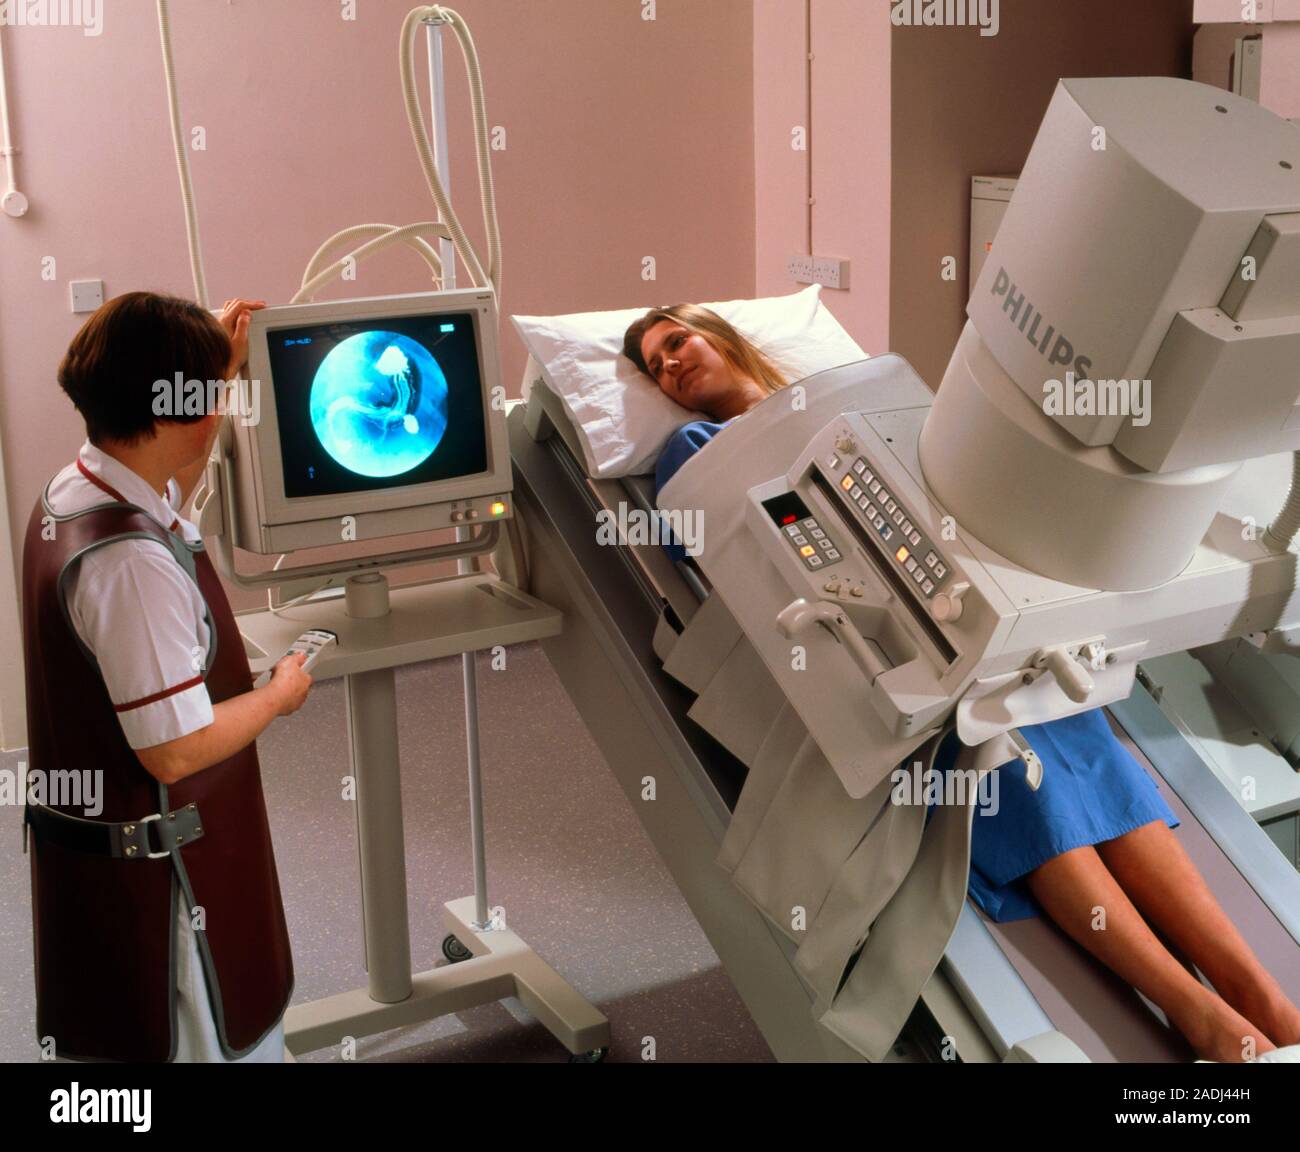

Процедура рентгенологического исследования

Следуйте указаниям рентгенолога для правильного позиционирования тела.

Рентгенологическое обследование в современном помещении

Рентгеноскопия в IDM Clinic